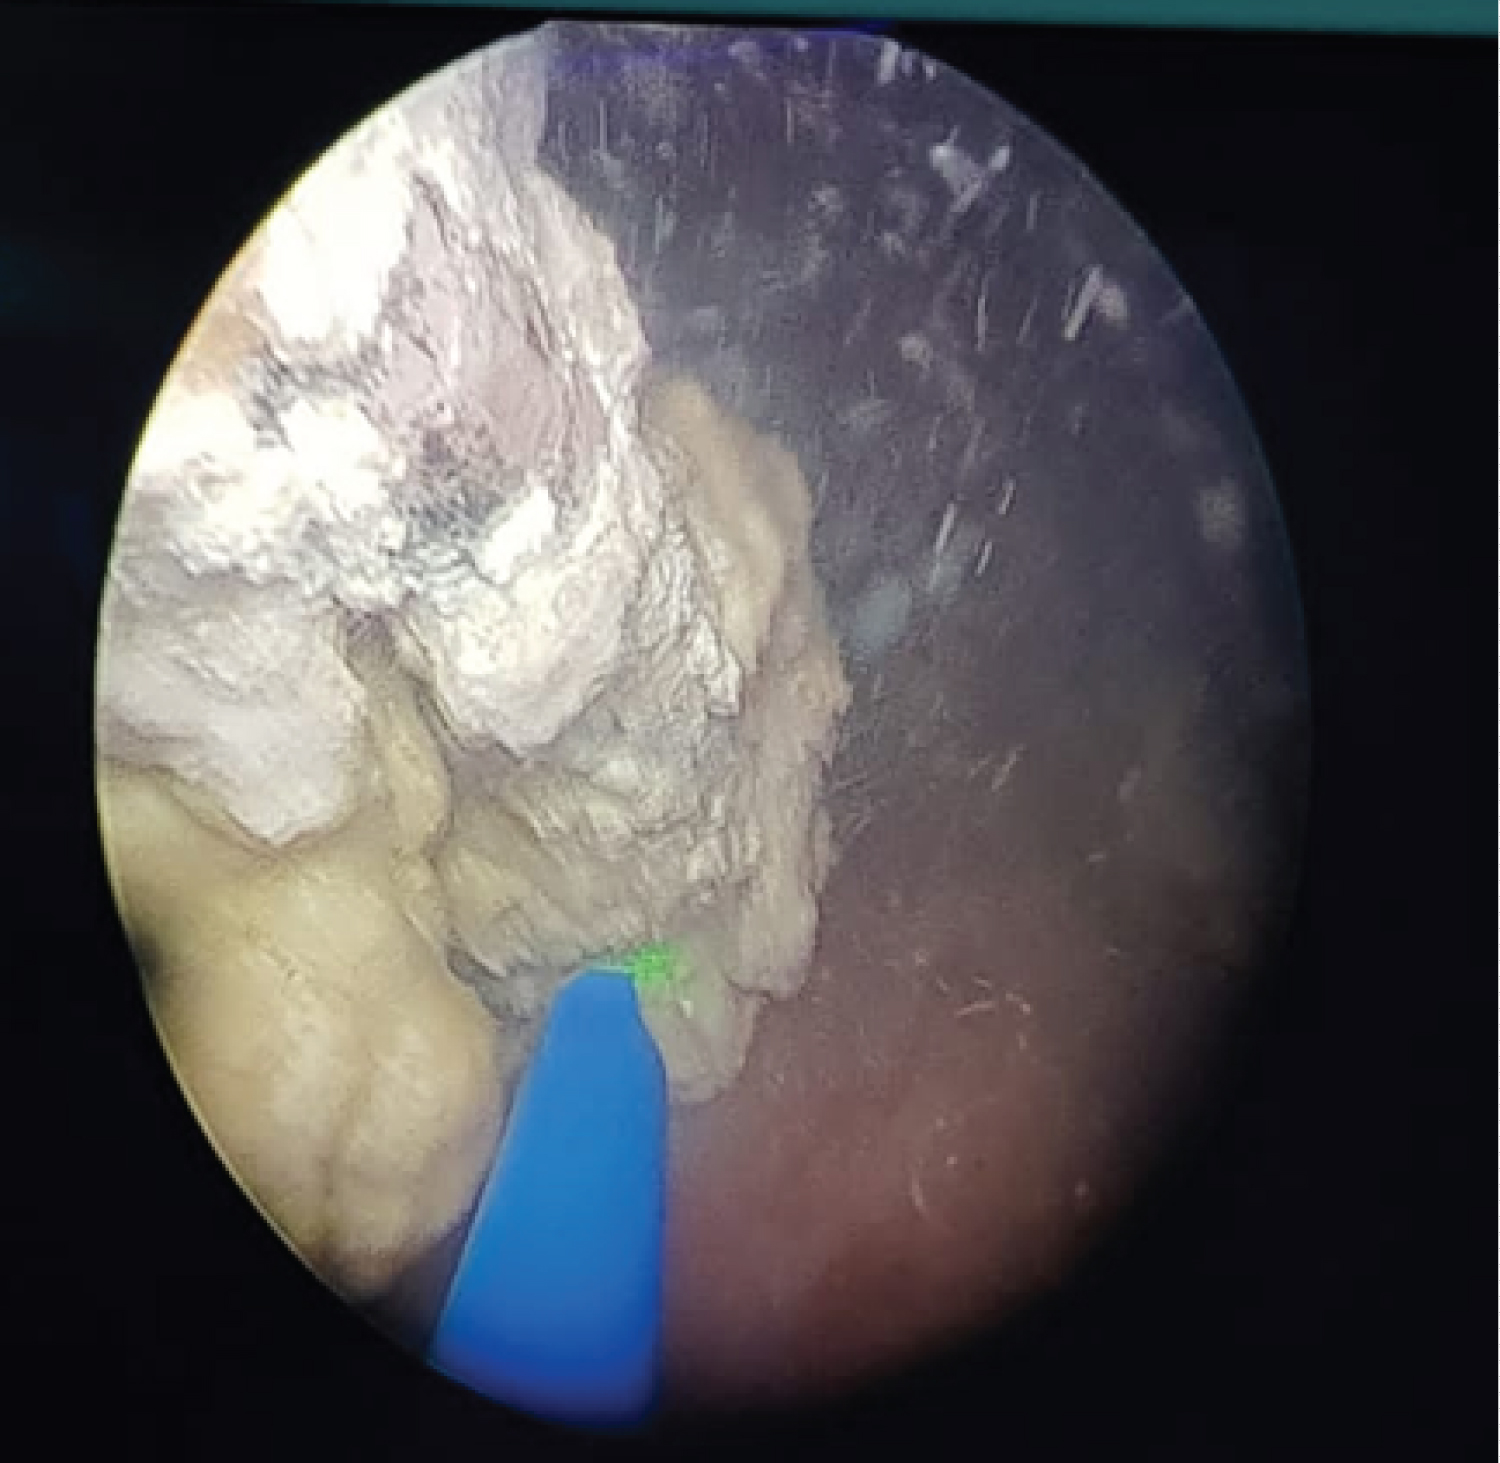

Biologically, an infectious syndrome is associated with renal failure. Capillary blood glucose was 3.2 mg/dl with 7% glycated haemoglobin. The emergency procedure was the setting up of a bilateral nephrostomy, antibiotic therapy, rehydration and glycemic control. At a distance from the acute episode, a laser fragmentation (Figure 2) of the intra bladder and ureteral calcification was first performed and then a pyelolithotomy for extraction of the encrusted renal stones with double J stenting (Figure 3).

Figure 2: laser fragmentation of calcifications. View Figure 2

Figure 3: Intraoperative vision and the extracted stent. View Figure 3